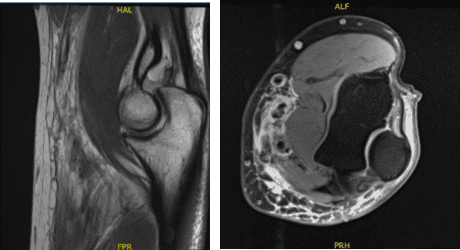

For previous surgery, he reported none. The patient’s MRI result was reviewed and discussed. The results showed biceps tendon rupture and lateral epicondylitis.

MRI 3T Left Elbow non-contrast